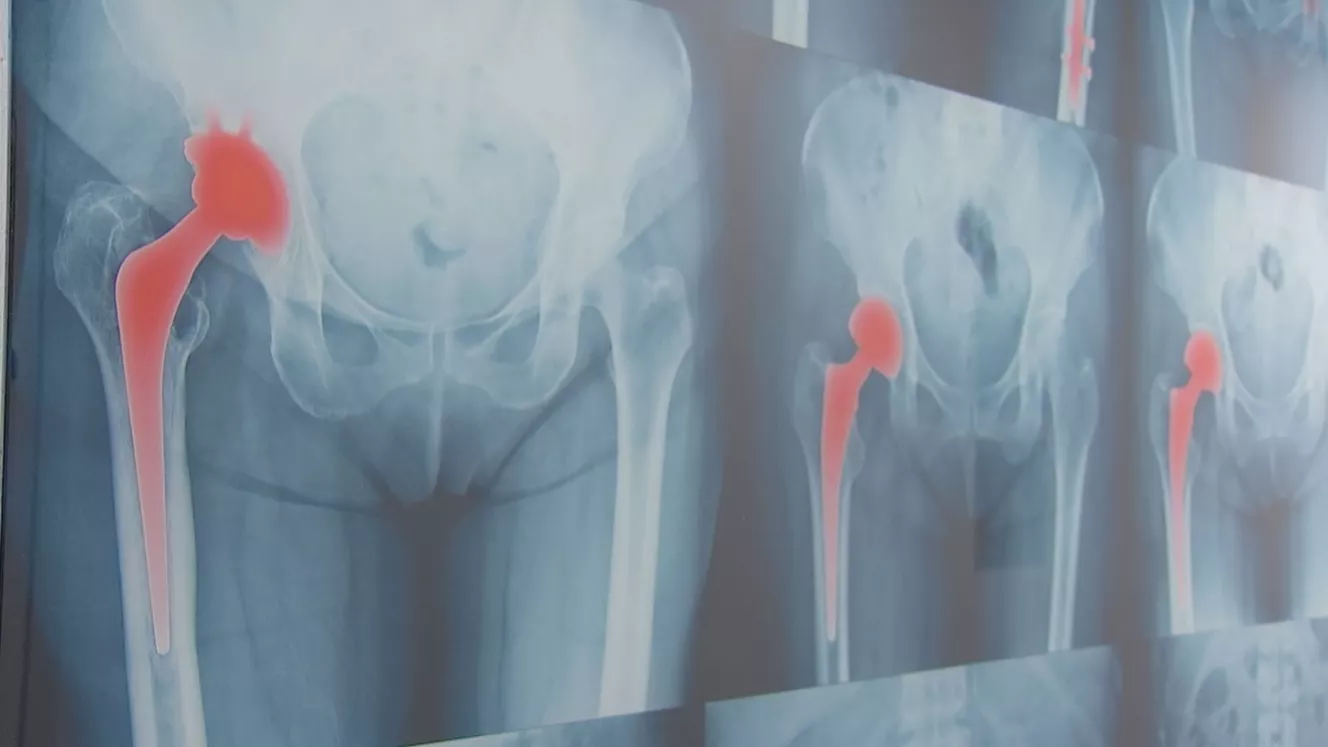

Moderne Behandlungsmethoden: der Weg zum neuen Gelenk

Künstliche Gelenke können eine neue Lebensqualität bringen. Aber für welchen Patienten macht es Sinn? Eine Informationsveranstaltung will diese und andere Fragen beantworten.

Jungen, die im Jahr 2020 geboren sind, werden – laut dem Statistischen Bundesamt – 78 Jahre alt. Mädchen sogar 83 Jahre. Allerdings hat die Natur nie vorgesehen, dass wir Menschen so alt werden. Und genau wie bei unseren Autos, muss man früher oder später über „Ersatzteile“ nachdenken. Besonders unsere Gelenke unterliegen einem Verschleiß. Moderne Medizin-Technik kann hier helfen. Aber bei welchen Patienten bringen neue Gelenke eine neue Lebensqualität? Genau diese und weiter Fragen sollen bei der Informationsveranstaltung des Endoprothektizentrums am 14. Dezember beantwortet werden. Die Kliniken Nordoberpfalz und das ONZ Weiden wollen über die heutigen Möglichkeiten aufklären. Dabei geht es um die Frage, wann ein neues Gelenk Sinn macht, wie der Eingriff und die Reha ablaufen. Aber auch die Frage was passiert, wenn ein neues Gelenk altert und ersetzt werden muss, wird beantwortet. Die Veranstaltung findet am Dienstag, 14.12.2022 zwischen 18 und 19 Uhr in der Personalcafeteria des Klinikums Weiden (Gabelsbergersstraße / Am Schwesternwohnheim) statt.